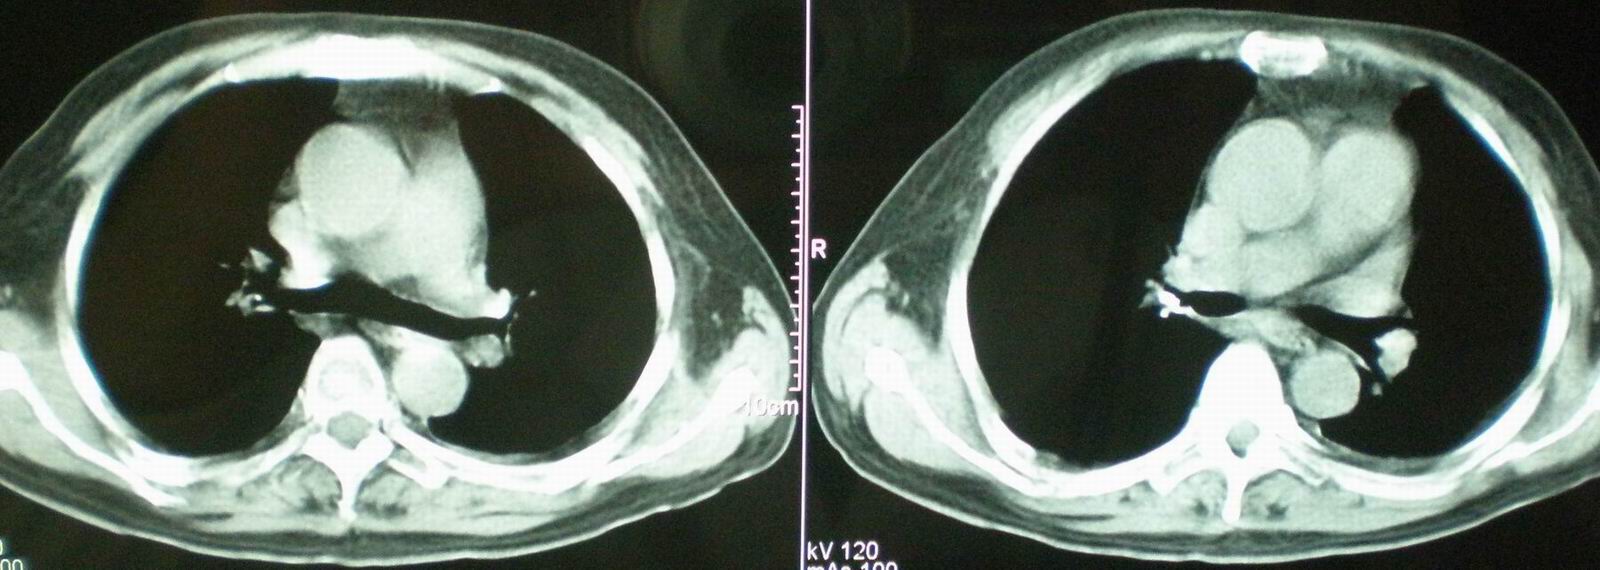

2008年11月18日今天的ct片

2008年9月18日ct片

2008年9月8日ct片:

机遇性感染!不除外急性肺水肿!

急性心衰所致肺水肿,双侧胸腔积液,少量心包积液可能?结合临床及其它检查.

我仔细看了下病人的出院小结,当时情况危急,诊断里有1型呼衰。心包周围的是脂肪密度。结合三次ct扫描的图象分析,个人认为:1、病人目前肺部病灶基本消失,双侧胸腔内少量积液,抗结核治疗才一个多月,就算是结核,抗结核治疗有效果,为何效果如此好,一点纤维灶的痕迹都没有呢,再就是患者做过气管镜检查及活检、痰检均未找到结核的证据。所以不支持结核的诊断。

2、结合现在的ct片,考虑:肺水肿及真菌感染,双侧胸腔积液。

急性呼吸窘迫综合征,肺水肿,与激素减量太快有关.双侧胸腔积液.